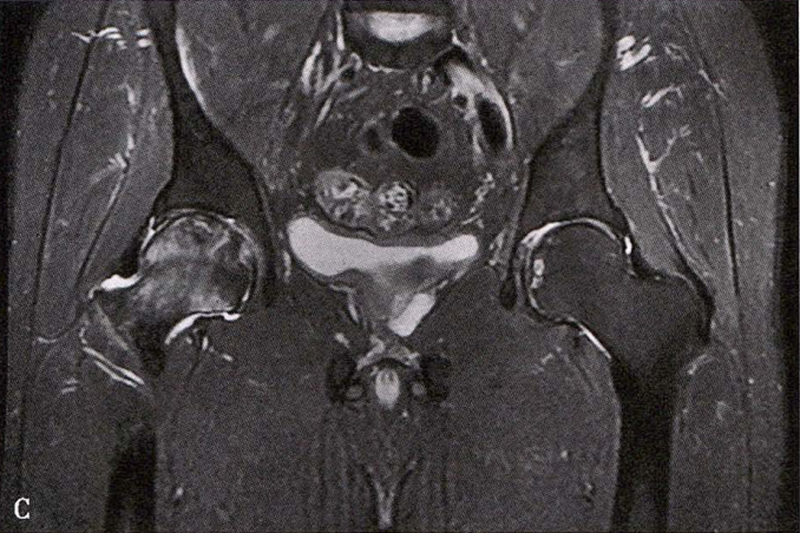

C.女性,89岁,右侧股骨头坏死Ⅳ期。X线片示右侧股骨头压缩变扁,右侧髂臼密度增高,关节内侧间隙狭窄、不均匀(C1)。MRI示右股骨头压缩变扁,右髋关节腔比较多积液(C2)。